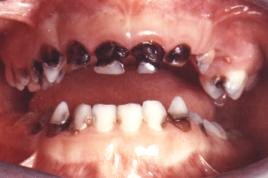

Alle fakta viser, at fluorid ikke har noget med cariesfrihed at gøre. Og cariesfrihed er det vi ønsker for risikopatienterne og alle andre. Netop for risikopatienterne er forskernes forbryderiske udtalelser gift. Når man har set små børn med masser af huller, skrigende af smerter og angst i tandlægestolen; og man ved, at fluor er medvirkende årsag, fordi det får folk til at slække på plakfjernelsen. Så undrer man sig over, at myndighederne tillader, at kvaksalvere, der burde sidde bag tremmer, går frit omkring. At kalde det videnskabelig uredelighed er århundredets underdrivelse.

Med kampagner og anbefalinger om fluor og sukker er der sat spørgsmålstegn ved tandplejens reelle hensigter. Det er kun regelmæssig plakfjernelse der kan give cariesfrihed. Alle andre metoder kan kun medføre en sænket cariesprogressionshastighed. Sålænge der er plak på tænderne vil der være caries. Uden plak er der ingen caries, helt uafhængigt af fluor og sukker. Stadig flere er cariesfrie, en cariesfrihed som helt uden tvivl er opnået ved bedre plakfjernelse. Men der er stadig risikopatienter med caries som har brug for bedre regelmæssig plakfjernelse. Den plak der er årsagen til caries på risikopatienternes tænder, har de netop på grund af den forvirring som kvaksalverne skaber omkring plakfjernelse med sukker og fluor. De har ikke skyggen af bevis for at de cariesfri bruger mindre sukker eller mere fluor. Vi burde for længst have været cariesfrie allesammen. Men sålænge kvaksalverne får lov til at udbrede deres løgne, vil der være ofre der falder for dem. Små børn vil til stadighed komme grædende til tandlægen med huller i tænderne forårsaget af plak der ikke er blevet fjernet på grund af de skadelige fluor- og sukkerkampagner.